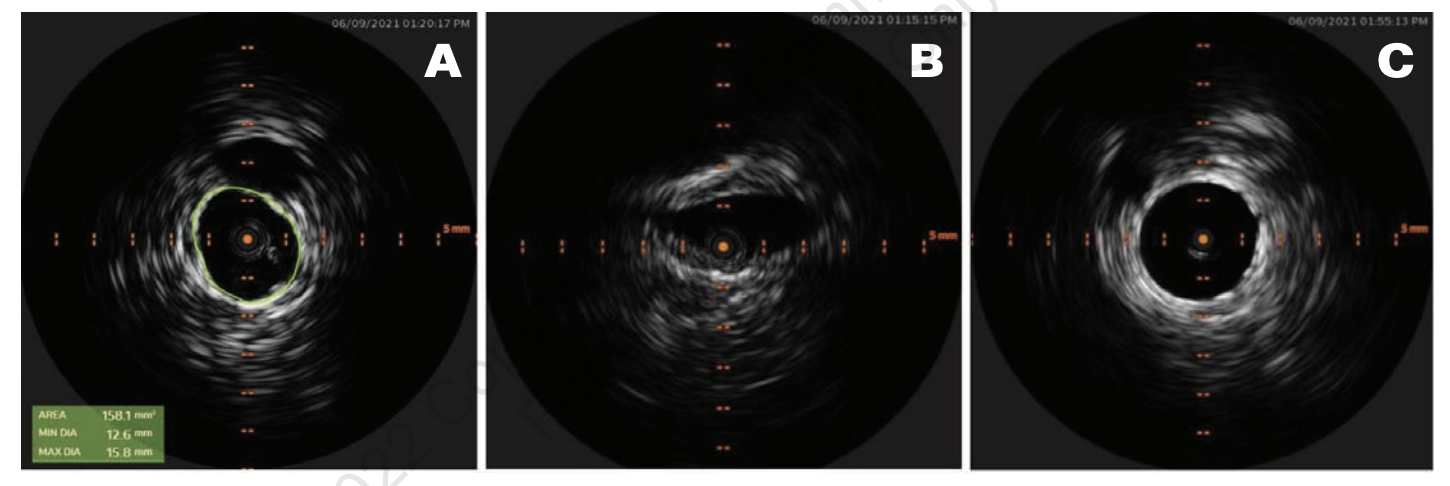

A 39-year-old woman with a history of recurrent deep vein thrombosis (DVT), pulmonary embolism (PE), and protein C deficiency on oral anticoagulation (OAC) was referred to our clinic for chronic bilateral lower extremity swelling, redness, and varicose veins. She was initially diagnosed with DVT and PE in 2003, for which she was on OAC with warfarin. Her warfarin was discontinued 6 months later, and she did well until 2018 when she had a recurrent DVT and PE following an 8-hour plane ride. At that time, a workup revealed a protein C deficiency, and she had been on OAC with apixaban 5 mg twice daily ever since. Her leg swelling, redness, and pain became severe a few weeks before presentation, which was aggravated by standing for long periods. She also complained of frequent dyspareunia and periodic pelvic pain. On physical examination, she was noted to have varicose veins on both legs, 2+ pedal edema up to the level of the thigh, and redness in both legs. We ordered a venous ultrasound (US) of the lower extremity to assess for reflux and to rule out DVT. We ordered a magnetic resonance angiography (MRA) with the suspicion of a central venous obstruction and PCS. Her US showed a chronic, nonocclusive thrombus in the left common femoral vein (CFV). Her MRA showed effacement of the proximal left iliac vein by the right common iliac artery, which was consistent with May-Thurner syndrome (Figure 1). In addition, the MRA showed varices of the anterior pelvic wall. We performed venography with intravascular US (IVUS)-guided percutaneous transluminal angioplasty (PTA) and stent placement. US-guided access was obtained from both right and left popliteal veins, and 8 Fr sheaths were inserted. Contrast venography was performed to both the deep femoral and iliac veins, demonstrating vessel patency throughout with visually apparent luminal narrowing in the left iliac vein. IVUS confirmed a 40% compression of the right external iliac vein (EIV) and a diffuse 80% fibrotic stenosis of the left common iliac vein (CIV) to CFV (Figure 2A). Extensive pelvic collaterals were also noted (Figure 2B). We performed PTA of the left CIV with a 16 mm x 40 mm Atlas Gold balloon (BD). Following balloon angioplasty, through the 8 Fr sheath, we deployed a 16 x 140 mm Zilver Vena stent from the left CIV into the EIV and deployed another 16 x 60 mm Zilver Vena stent overlapping with the first stent from the EIV into the CFV. The stents were post-dilated with the same Atlas Gold balloon, and a postprocedure venogram and IVUS showed excellent results, with complete resolution of the pelvic collaterals (Figure 2C). She was discharged home on clopidogrel 75 mg daily in addition to the apixaban 5 mg twice daily that she was already on. On a follow-up visit 1 month later, the patient reported significant reduction of her lower extremity edema, pain, and redness. On a 6-month follow-up, she reported complete resolution of these symptoms as well as pelvic pain and dyspareunia.